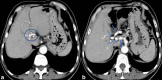

The Abernethy malformation consists of a congenital extrahepatic portosystemic shunt and is believed to be extremely rare in humans. The potential implications of abnormal portovenous shunting and decreased hepatic portal flow are numerous and potentially serious. Although congenital extrahepatic portosystemic shunts are increasingly suspected and diagnosed in specialized centres, much of their clinical presentation and natural history is not fully understood. Symptoms of portosystemic shunt are mainly caused by increased levels of ammonia, which lead to signs of encephalopathy. Therapeutic options depend on the type of shunt and its clinical course, so the classification of the congenital portosystemic shunt is a key finding in these patients.